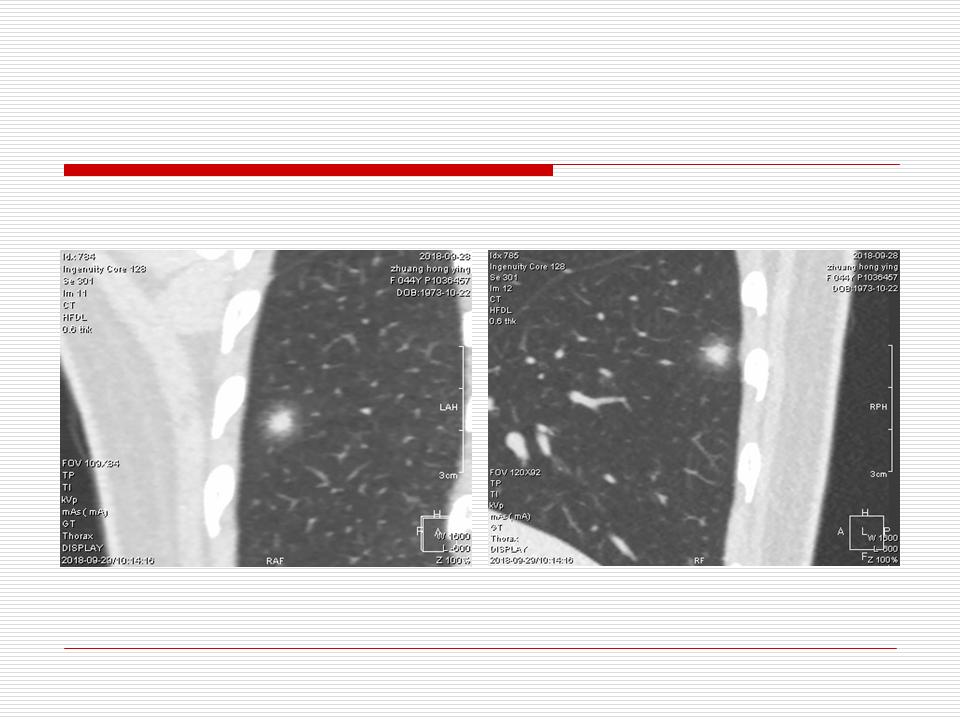

肺部阴影永恒且最重需要鉴别的是:到底是炎症还是肿瘤?但临床的病例中的影像表现难以界定或有些肿瘤特征,同时又有些炎症特点是非常常见的情况。作为临床医生我们怎么去总结分析,并找到之所以是炎症或之所以是肿瘤的细微差别或特点非常重要,也非常有用。2019.12.7浙江省2019年胸心外科学学术年会在宁波召开时,我的临床病例分析与经验总结<那些像肺癌的炎症与像炎症的肺癌>获得在大会交流的机会,以下为该PPT的内容,与你分享,希望对同道有益,有借鉴与启迪。若有探讨与进一不完善的建议,欢迎文末留言讨论: